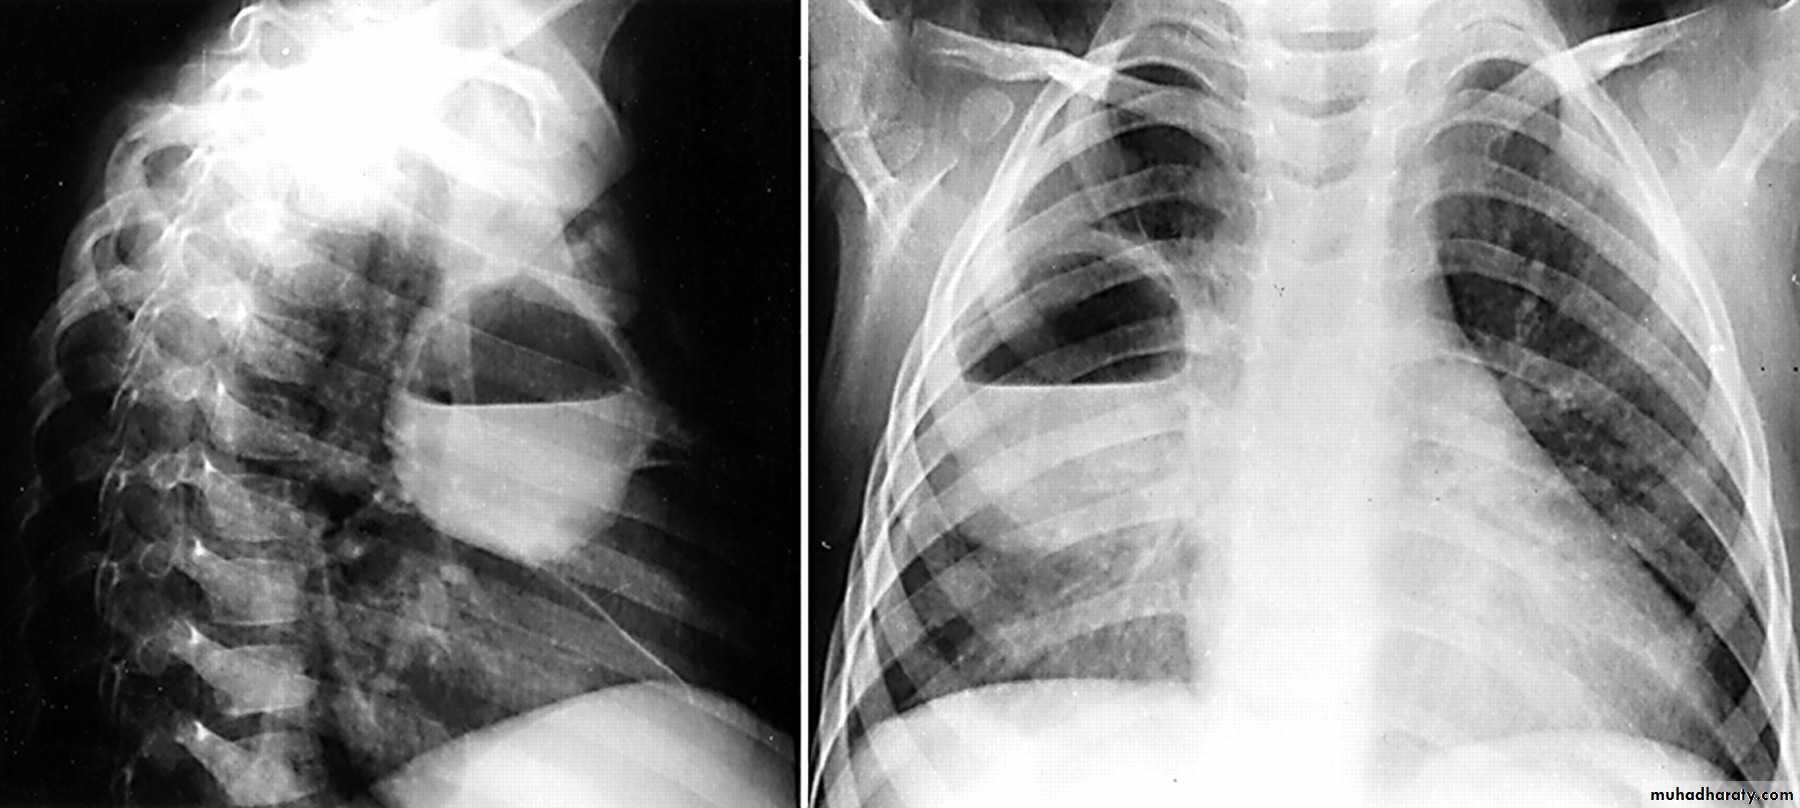

Pancosts tumor

A Pancoast tumour, otherwise known as superior sulcus tumour, refers to a relatively uncommon situation where a primary bronchogenic carcinoma arises in the lung apex and invades the surrounding soft tissues , adeno CA being the most frequent type ,Plain film

Plain films demonstrate a soft tissue opacity at the apex of the lung. Occasionally with rib involvement with extension into the supraclavicular fossa may be evident with surrounded bony destruction . Lordotic views may be helpful .

Must important complication is involvement of the sympathetic chain >>>>

* Ptosis

* Meiosis

* unhydrosis

Pancost tumor